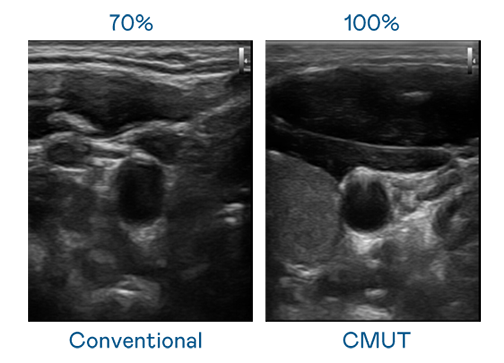

CMUT 技術是一種用電容式微機電元件來產生超音波訊號的技術。與傳統 PZT 壓電式技術相比,CMUT 頻寬增加 30%,更寬頻的超音波訊號讓影像解析度大幅提升,是實現高影像品質醫療超音波掃描、促進精準醫療發展的關鍵技術。

大頻寬帶來超清晰影像

超音波影像的解析度高低,首先取決於探頭能發出的訊號頻寬。六合联盟 CMUT 可提供高清晰的超音波訊號,提供高頻寬、高靈敏度、影像紋理細節更高的超音波影像,協助醫護人員縮短影像判讀時間及利用精準的醫療影像進行診斷。